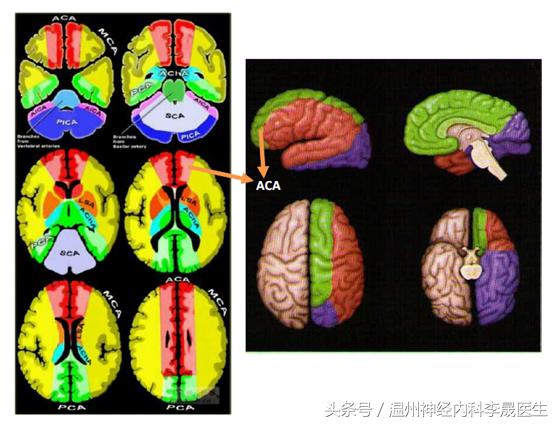

首先看看前动脉的供血区域,左图红色,右图绿色区域就是大脑前动脉的供血区域

细分前动脉的分支(关注我晚上发的大脑前动脉思维导图)